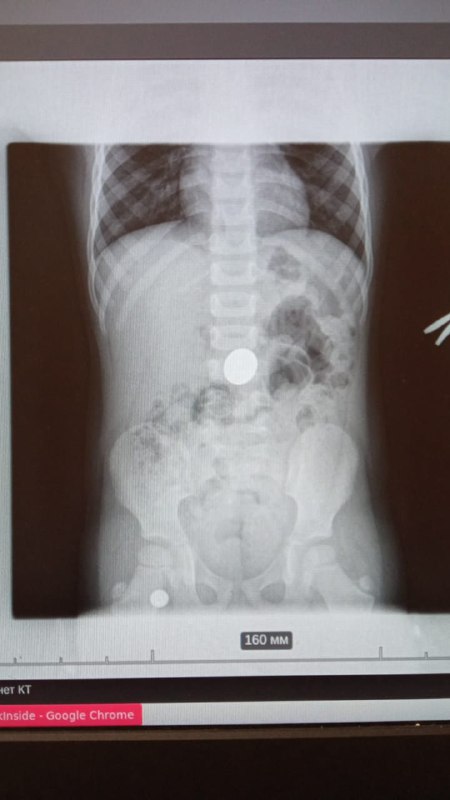

«Рентген подтвердил: ребенок проглотил пятирублевую монету, — рассказывает врач-эндоскопист Гор Саакян, который проводил процедуру извлечения инородного предмета.

— Мальчик поступил вечером, его положили в хирургическое отделение. Контрольный снимок рентгена, сделанный утром показал, что монета осталась на прежнем месте. Было принято решение извлекать безоперационным способом. Была проведена лечебная гастроскопия под эндотрахеальным наркозом. Монету извлекли, ребнок уже выписан — состояние его здоровья удовлетворительное. Сегодня такие процедуры извлечения инородных предметов, проглоченных пциентами, проводятся на высоком уровне благодаря современному медицинскому оборудованию, которым оснащена ТЦРБ № 1».

Это — седьмой случай за год, когда туапсинским врачам приходится извлекать проглоченные предметы. Большинство пациентов, поступающих с таким диагнозом — дети.